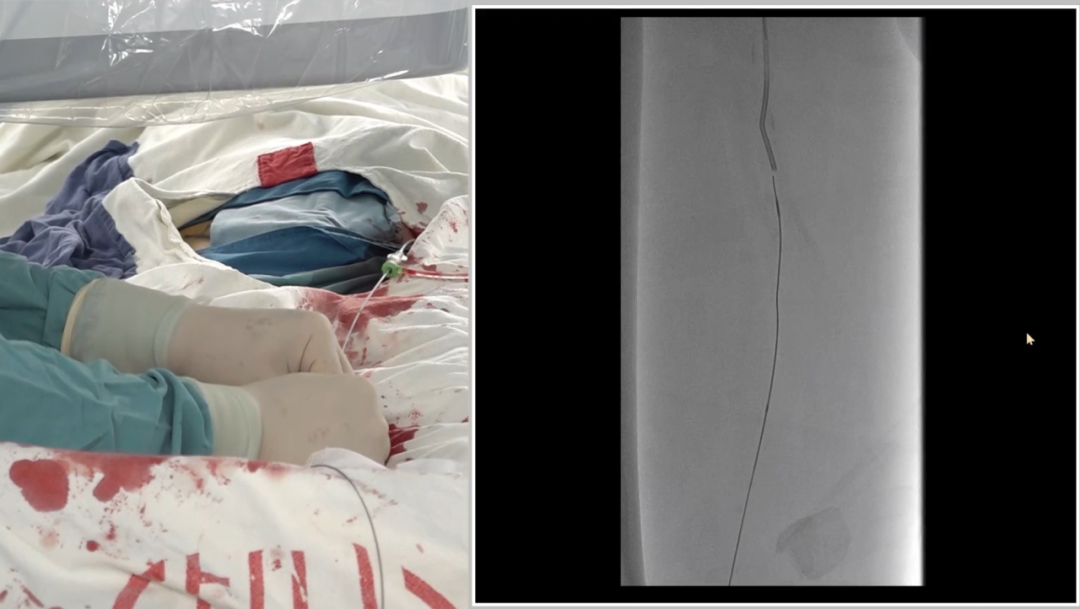

入路选择:左侧股动脉翻山入路

采用常规左侧股动脉穿刺,通过"翻山"技术到达右侧病变区域,为后续操作建立通路。

导丝进入远端内膜下后,反复尝试返回真腔失败。为避免过度操作损伤远端流出道,团队决定行逆向穿刺(逆穿):

调整球管至左前斜20°~30°,在路图下定位穿刺点;

近端推注造影剂,透视下确认血管位置,穿刺成功(可见明显充盈缺损);

跟进V18导丝突破远端纤维帽,配合支撑导管完成对接。

逆穿的难点在于选择合适的对接位置,对接判断要点是导丝成袢后,通过近端Terumo导丝触碰,若有明显"碰触感",提示位于同一内膜下,可确认对接。